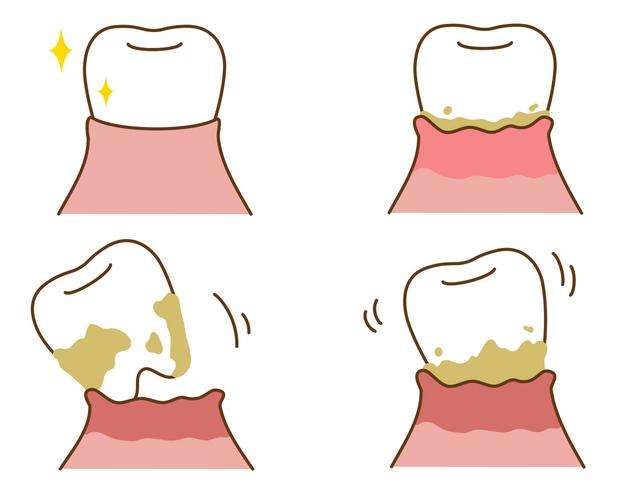

都说贴秋膘好过冬,对于广州街坊来说,现在正是贴秋膘的时候。但是想要贴好秋膘,各位街坊还得需要一副好牙齿。有些街坊贴秋膘就是打火锅、吃烧烤,怎么好吃怎么来,只要能大口吃肉就满足了。但吃完这些“上火”的食物后,大家的牙齿就开始“报警”了,牙齿疼痛难忍。实际上,这往往是牙周病在作祟。因为秋季的干燥气候,唾液分泌减少,口腔细菌滋生速度上升,容易引起牙龈炎、牙周病等口腔问题。